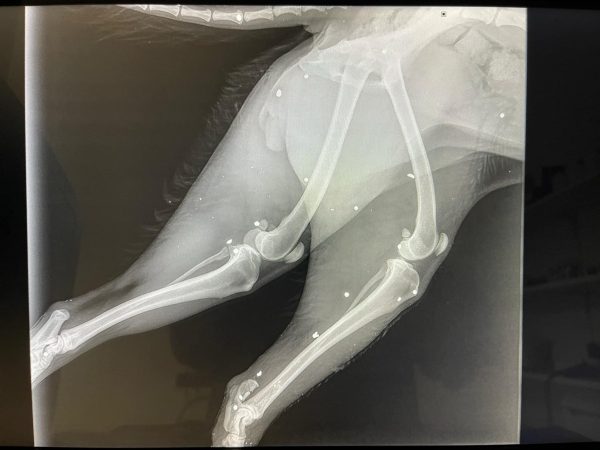

Οργή και αποτροπιασμό προκαλεί η άγρια κακοποίηση μιας μικροακαμωμένης σκυλίτσας στην Κρήτη. Από σπασμένα κόκκαλα μέχρι σφαίρα βρήκαν οι κτηνίατροι στο σωματάκι της, στο Αρκαλοχώρι Ηρακλείου. Με 3 πόδια πλέον το ζώο προσπαθεί να επανέλθει, την ώρα που οι δράστες παραμένουν άγνωστοι.

Σύμφωνα με το τοπικό Flashnews, η σκυλίτσα βρέθηκε σοβαρά χτυπημένη, με τα κόκκαλα στο ένα της πόδι κυριολεκτικά θρυμματισμένα, ενώ το οστό φαίνεται εκτεθειμένο. Παράλληλα, στο σώμα της βρέθηκαν σκάγια, τα οποία επιβεβαιώνουν πυροβολισμό!